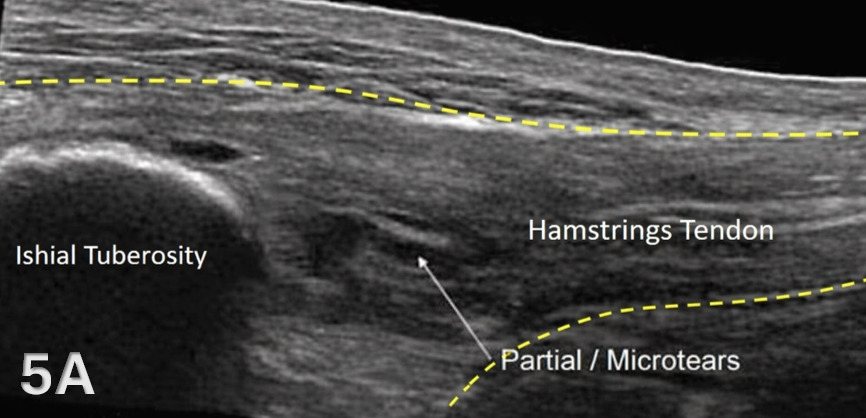

Disruption of fibrillar pattern in partial tears and ruptures. Proximally, it is important to determine if the injury is a free-tendon injury or purely a myotendinous injury.20

The starting point for examining the proximal hamstring tendon and muscle is at the osseous landmark – the ischial tuberosity.12,13,17–19 The ischial tuberosity can almost always be palpated, giving the examiner a perfect location to begin their scan. The proximal hamstring can be scanned in both the long axis (LAX) and the short axis (SAX). In the LAX view, depending on the probe width and size, one should start proximally to visualize the hyperechoic reflection of the bony cortex of the ischial tuberosity, with its large acoustic shadow underneath. In LAX, the proximal hamstring tendon fibers of the long head of the biceps femoris and the semitendinosus conjoint tendon should be easily seen coming off the attachment of the ischial tuberosity with a clear hyperechoic fibrillar structure running distally from the insertion site on the anterior lateral origin of the ischial tuberosity. The semitendinosus fibers can be easily seen as they reach the ischial tuberosity directly. Lateral to the hamstring muscle complex, the sonographer will see the sciatic nerve that appears as a fascicular, flattened structure that descends between and deep to the long head of the biceps femoris and semimembranosus tendon.1 The probe can be turned 90 degrees for viewing in the SAX. If the probe is moved slightly distally in the SAX view, the biceps femoris will appear as a triangular shape. As the examiner moves distally along the biceps muscle belly, the size will decrease until it appears to disappear. In both views, some toggling may be required to reduce anisotropy.